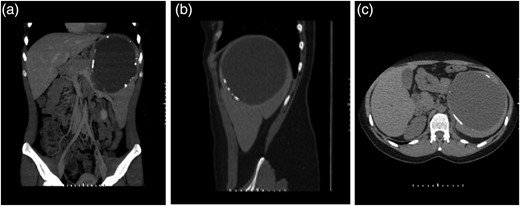

A 24-year-old woman with negative medical and surgical history, complaining of epigastric discomfort and associated nausea and occasional vomiting underwent abdominal ultrasound evaluation for suspicion of gallstone disease. The ultrasound results, further confirmed by computed tomography (CT) scan (Fig. 1a–c), revealed a large 16 × 12 cm splenic cystic mass. She was referred to Poissy Hospital (Paris) for surgical management of the splenic cystic tumor. The decision was made to perform laparoscopic splenectomy, with high suspicion of splenic hydatid cyst. Preoperative laboratory workup including Complete Blood Count, parasitic serologies and chemistries were within normal limits. Pneumovax 23™ 23-valent pneumococcal polysaccharide vaccine was administered 2 weeks prior to the planned splenectomy. Under general anesthesia, with the patient in the right decubitus position in reverse flexion, the abdomen was prepped and draped in the usual manner. Pneumoperitoneum was induced through a left sub-costal Veress needle insertion. A 10 mm camera port was inserted in the umbilical area. A 12 mm trocar was inserted in the sub-costal anterior axillary line. Another 5 mm trocar was inserted in the left sub-xiphoid area and a 5 mm trocar was inserted in the sub-costal mid axillary line. Exploration of the abdomen revealed a large splenic mass occupying the left flank and the epigastrium, covered with patchy white membranes. The rest of the spleen was lying posterior and inferior to the tumor and no other abnormalities were detected. Using Echelon Endopath™, a white endostapler, the splenocolic ligament was dissected exposing the left gastroepicloic artery, which was clipped and cut. Then the splenic hilum was dissected after retracting the spleen cephalad. The splenic vasculature was of bundled type with one major splenic artery, which was identified superior to the splenic vein. Both were dissected, clipped and cut making sure to preserve the pancreatica magna artery. Then dissection was carried on along the greater curvature of the stomach, where the short gastric were also cut. In order to completely mobilize the spleen, the splenophrenic ligament was also cut. A small hole was punctured into the wall of the cyst, through which 1.1 l of chocolate-colored liquid was entirely contained and suctioned to be sent for cytology followed by extensive irrigation with cetrimide ensuring no contamination. A fragment of the wall was sent to frozen section and was histologically identified as organized calcified hematoma with negative cytology. The spleen and the remainder of the cystic tumor were removed through a small incision in the left lower quadrant. A Hemovac™ suctioning device was left in the surgical site. The postoperative period was uneventful. The patient received prophylactic antibiotic treatment with 1.2 g of Amoxicillin/Clavulanic acid (Augmentin™) IVDrip every 12 h for six doses and the drain was removed on the fifth postoperative day. The patient's platelet count on postoperative day 6 was 620 000/µl. Consequently, 75 mg of acetylsalicylic acid (Kardegic™) was started once daily. The patient was discharged on postoperative day 7.

CT scan of the abdomen and pelvis without contrast, showing the 16 cm splenic cyst with partially calcified rim. (a) Coronal view, (b) saggital view, (c) cross-sectional view.